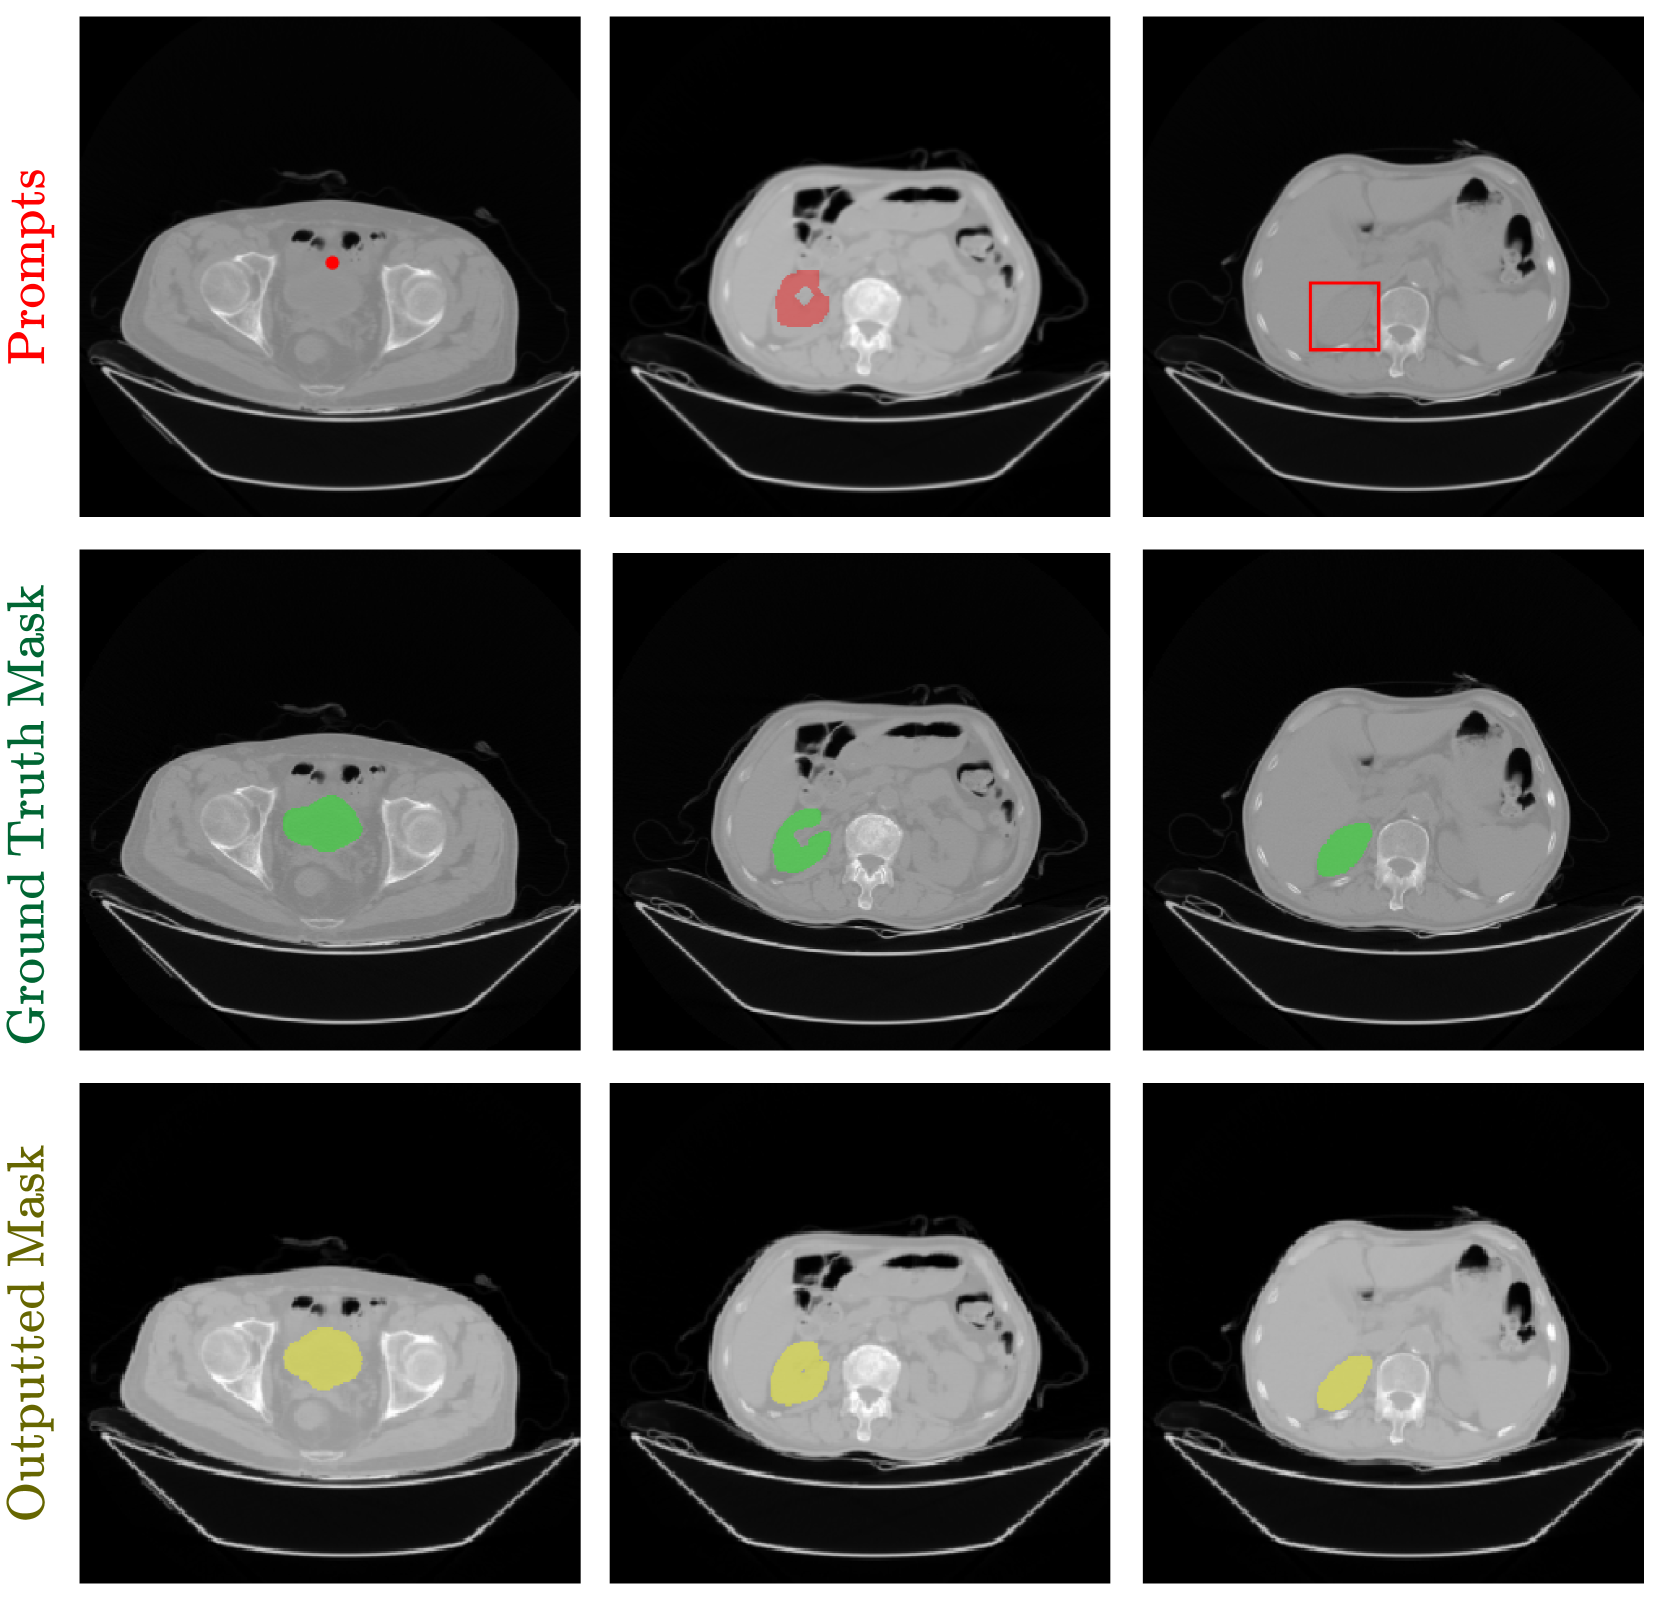

Figure 7 shows a qualitative example of our model’s predictions for each type of prompt: point, box, and mask. We display the prompt, the ground-truth mask, and the model’s prediction. We show additional qualitative examples in the supplementary materials.

Refer to caption

Figure 7: Qualitative results from various prompts. The prompt example appears in red, and on top, the ground truth mask appears in green under. At the bottom in yellow is the mask predicted by the model.